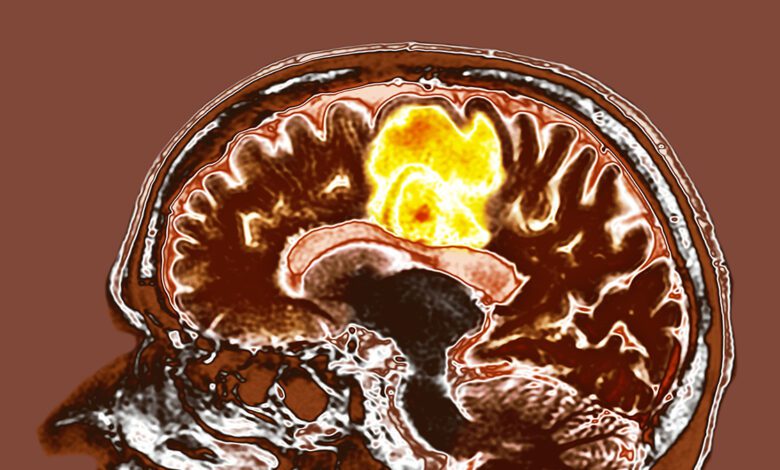

Glioblastoma is one of the most aggressive and hard-to-treat brain tumors. Despite advances in therapy, the prognosis for patients with this diagnosis remains extremely poor. However, new clinical trial data from India offer hope for new treatment strategies. The focus is on the combination of two accessible nutraceuticals: resveratrol and copper.

No serious side effects from taking resveratrol and copper were observed during the study period. The clinical trial is ongoing: it aims to enroll 66 patients and monitor their condition through regular MRI scans over two years. Only when this phase is completed will it be possible to judge the impact of the supplements on patient survival and quality of life.